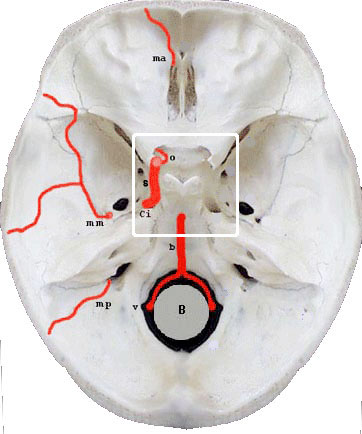

Base endocrnienne

-B: Bulbe

-b: tronc basilaire

-ci: carotide interne

-ma / mm / mp: artres mninges ant., moy. et post.

-o: artre ophtalmique

-s siphon carotidien